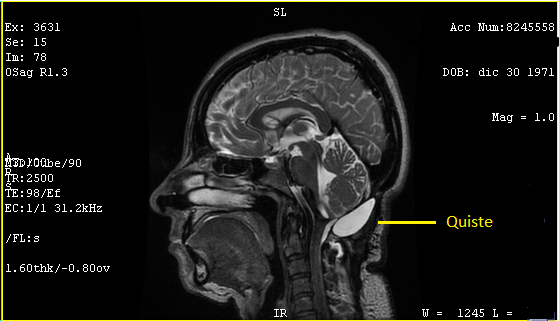

El 6 de agosto regresé con los resultados de la resonancia, análisis de sangre y orina, esta vez yo tuve los resultados primero, así que al verlo lo primero que dije fue "¿Qué pasa doctor que mi cuerpo sigue rechazando el parche?", la resonancia confirmó lo mismo el quiste media 4.2 x 1.7 x 2.9 cm y 10 centímetros cúbicos y la fistula 4.8 mm y el remanente del tumor es de 15.1 mm, en contraste con en el ultrasonido 4.1 x 3.0 x 1.6 cm y 11.04 centímetros cúbicos y la fistula 0.7 cm.

Afortunadamente el doctor estaba de mejor humor, porque mientras veía los resultados me contestó "Su cuerpo es muy chocosito que quiere, esto no tiene nada que ver con las cirugías, de eso está perfecta", me mostró que el remanente del tumor alojado en el tallo cerebral y cree que mi falta de equilibrio y náuseas tienen que ver más eso. El tallo cerebral regula las funciones vitales lo que significa que mi falta de equilibrio será permanente, de las náuseas no lo sabe.

"El quiste no ejerce ninguna presión en cerebelo o tallo cerebral, y el resto está perfecto no hay ningún daño" "Supongo que algo tiene que hacer con la fístula, no me puedo quedar así o sí?", "Bueno, no representa peligro alguno, ya que es la misma agua circulante, pero vas a regresar al medicamento que reduce el líquido del cerebro, usa la venda en las noches para hacer presión, evita cualquier esfuerzo o cargar cosas pesadas, porque solo generaría presión, en un mes vienes y vemos si se redujo el quiste y cerró la fístula y evaluamos si te ponemos una válvula".

Me lo imaginaba, la válvula era la tercera operación que se canceló en octubre del año pasado, en lo absoluto me agradaba la idea de tener que someterme a una tercera cirugía, pero si era necesaria para recuperar mi vida y retomar las cosas que amo lo haría sin duda, mi vida estaba limitada en muchos aspectos.